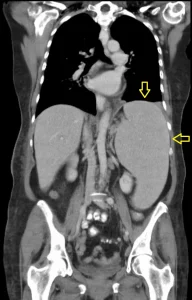

Além do exame físico, utilizam-se exames de imagem como ultrassonografia (USG), tomografia computadorizada (TC) ou ressonância magnética (RM) para o diagnóstico da esplenomegalia.

A esplenomegalia pode estar associada a doenças de origem neoplásica, infecciosa, metabólica, imunológica ou por acúmulo de substâncias. Uma causa comum é a cirrose hepática. Frequentemente, o aumento do baço ocorre em conjunto com o aumento do fígado — condição chamada de hepatoesplenomegalia.

O baço também pode aumentar devido à trombose da veia porta ou da veia esplênica, bem como por metástases esplênicas ou tumores primários. Entre as lesões focais, cerca de metade são benignas, sendo o infarto esplênico o mais comum. As metástases esplênicas ocorrem em cerca de 7 a 8% dos pacientes com neoplasias malignas, especialmente cânceres de ovário, útero, mama e pulmão.